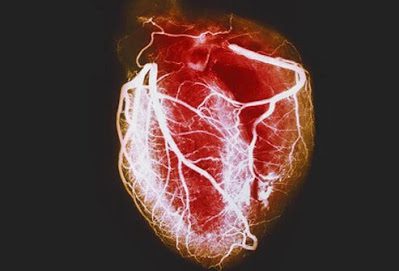

Η στεφανιαία νόσος είναι ένας κοινός τύπος καρδιακής νόσου και η κύρια αιτία καρδιακών προσβολών.

Στεφανιαία νόσο

Η στεφανιαία νόσος είναι η κύρια αιτία καρδιακών προσβολών. Είναι το πιο συνηθισμένο είδος καρδιακής νόσου στις ΗΠΑ.

Συμπτώματα στεφανιαίας νόσου

Η στεφανιαία νόσος εμφανίζεται όταν η πλάκα, μια κολλώδης ουσία, στενεύει ή εμποδίζει εν μέρει τις στεφανιαίες αρτηρίες (όπως το κολλώδες υλικό που βουλώνει ένα καλαμάκι) και μπορεί να οδηγήσει σε μειωμένη ροή αίματος. Αυτή η μειωμένη ροή αίματος μπορεί να προκαλέσει πόνο στο στήθος (στηθάγχη), ένα προειδοποιητικό σημάδι πιθανών καρδιακών προβλημάτων όπως καρδιακή προσβολή. Η πλάκα μπορεί επίσης να παγιδεύσει μικρούς θρόμβους αίματος, εμποδίζοντας εντελώς μια στεφανιαία αρτηρία ξαφνικά, με αποτέλεσμα καρδιακή προσβολή.